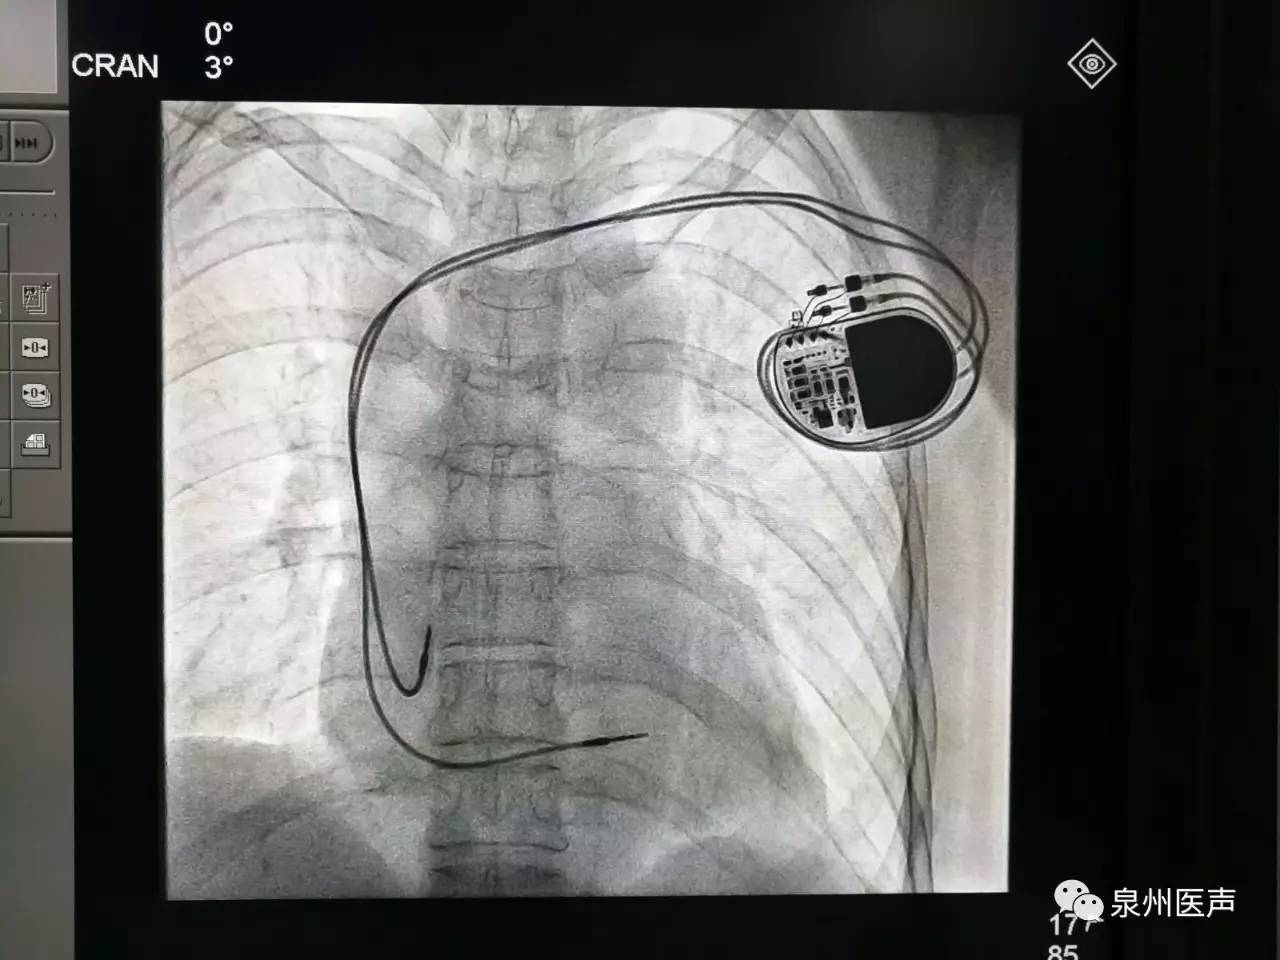

微創(chuàng)、樂普、先健填補國產(chǎn)起搏器市場空白,釋放哪些信號?

世界最小起搏器,正式進入中國市場!

器械之家曾做過專題報道的“世界最小起搏器”(嬰兒用除外)在經(jīng)過了漫長的中國本土臨床研究后,終于獲得NMPA批準,正式于中國上市!